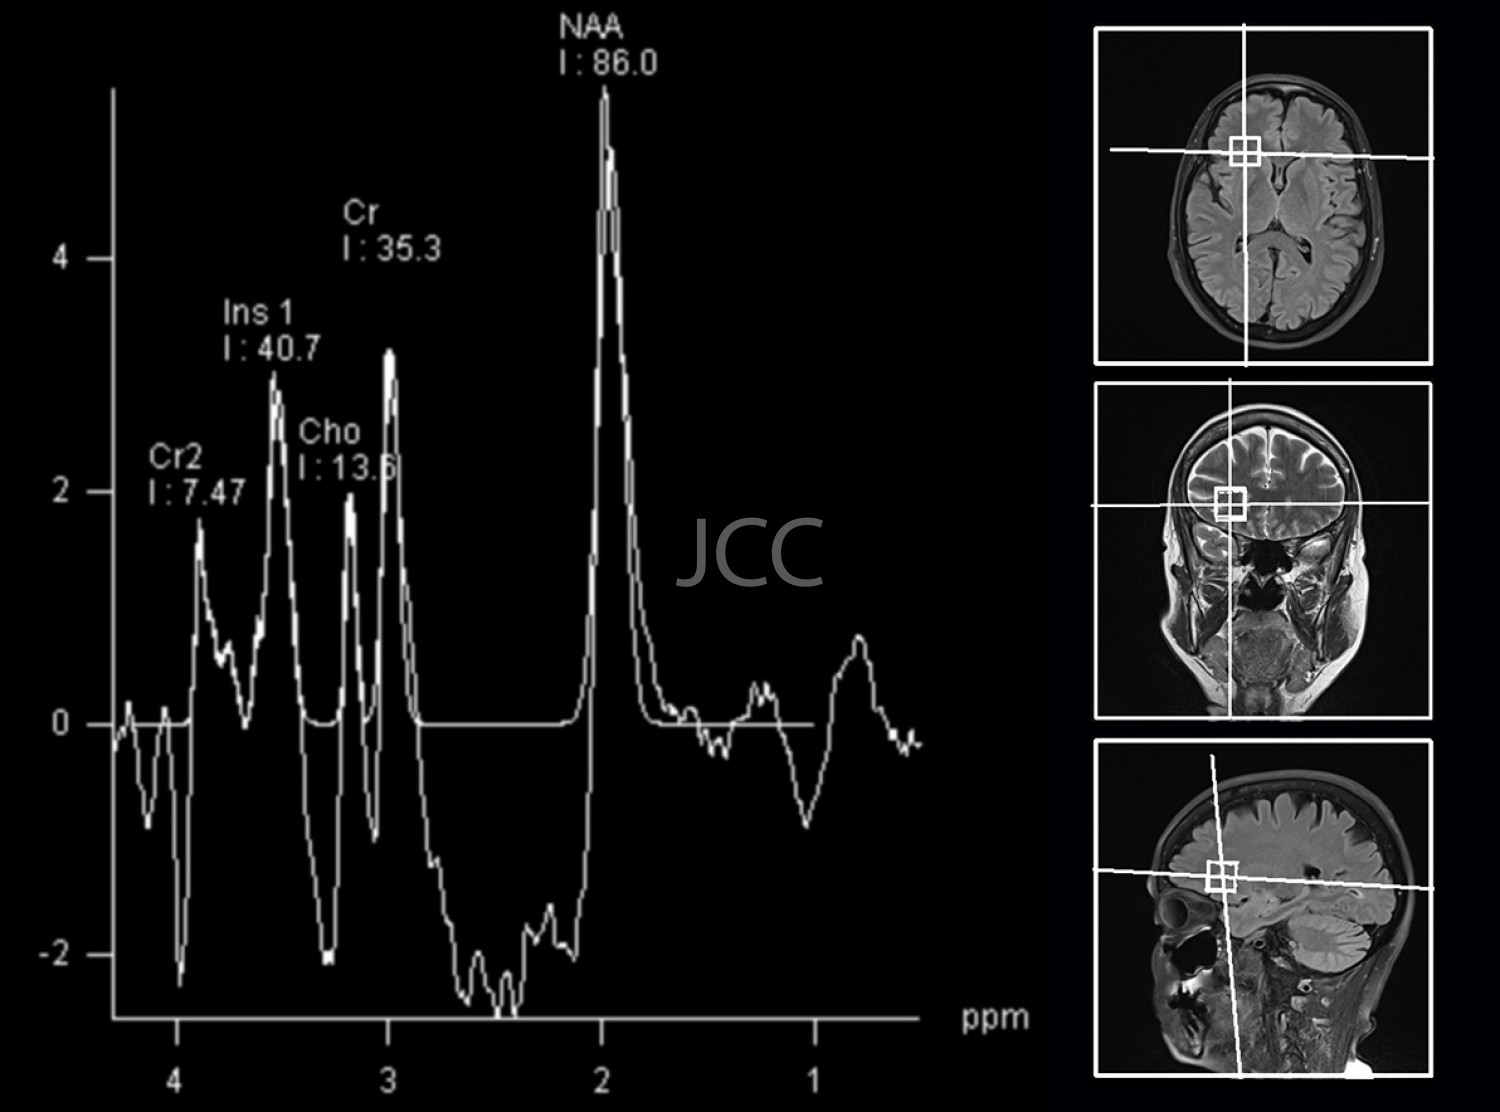

High Field Magnetic Resonance Imaging - Brain Spectroscopy

High-field magnetic resonance imaging (MRI) is an imaging technique that does not use radiation based on a magnetic field and radiofrequency waves to study the organs of the human body in detail.

Nowadays, with the most modern equipment of 1.5 and 3 TESLA it is possible not only to study the brain, the spine and joints, but it is also the technique of choice for vascular, heart, liver and pancreas evaluation.